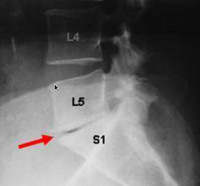

Pincement discal

Discopathie dégénérative

Notez la perte de hauteur discale

ou "pincement discal"